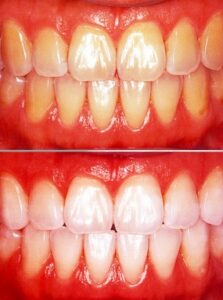

無料メール相談6(歯のホワイトニングしたいのですが、詰め物も白くなりますか?)

今まで、多くの方々に無料でメール相談をしてきました。その中から良くある相談を紹介しています。 「歯のホワイトニングをして白くしたいのですが、費用とか回数を教えてください。また、詰め物や差し歯も白くなりますか?」 これも、とてもよくある質問で […] 本文を読む